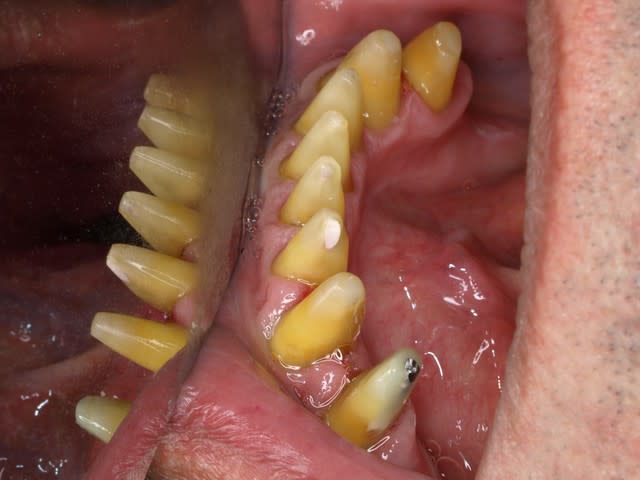

Les 2 images (toujours belle technique opératoire), vont peut être délier les langues (pas sûr que ce soit dans le sens que tu espérais). La aussi il serais intéressant de connaître le plan de traitement et les raisons de ce choix thérapeutique.

REPONSE: ci joint photos du depart.ttt un bridge de contention avec paro